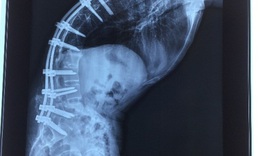

gù cột sống

Chế độ ăn có ích với người gù cột sống

Tra cứu bệnh - 13/04/2025 14:30SKĐS - Chế độ ăn đúng hữu ích trong việc hỗ trợ điều trị và quản lý gù cột sống. Duy trì ăn uống cân bằng, giàu dinh dưỡng có thể giúp duy trì sức khỏe xương khớp, giảm viêm và hỗ trợ quá trình phục hồi.